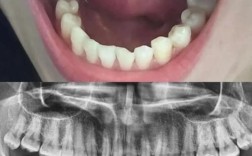

(图片来源网络,侵删)- 缺牙时间过长: 牙齿缺失后,牙槽骨会像肌肉萎缩一样逐渐被吸收(萎缩),高度和宽度都会减少。

- 术前评估: 通过口腔检查、X光片(全景片、根尖片)、CBCT(锥形束CT)精确测量骨缺损的范围和程度,制定详细的手术方案。